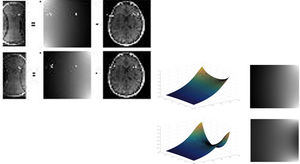

RACING

Reconstruction Augmentation by Constraining with Intensity Gradients (RACING)

PATENT

Ali Pour Yazdanpanah, Onur Afacan, Simon K. Warfield, Reconstruction Augmentation by Constraining with Intensity Gradients in MRI, Filed on April 25, 2019 with the U.S. Patent and Trademark Office as Application 62/838,452.

Sparse-View CT and MRI Reconstruction

Sparse-View CT and MRI Reconstruction Methods:

1- Compressed Sensing Magnetic Resonance Imaging based on Shearlet Sparsity and Nonlocal Total Variation (Link)

2- Compressed Sensing MRI using Curvelet Sparsity and Nonlocal Total Variation, CS-NLTV (Link)